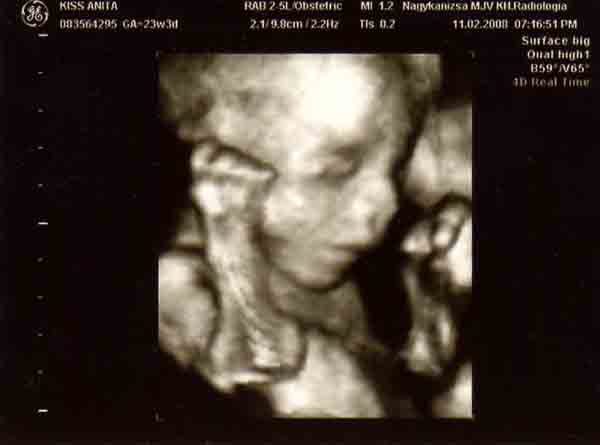

Banika: nagyon jok lettek a kepek!!! Olyan szepek!